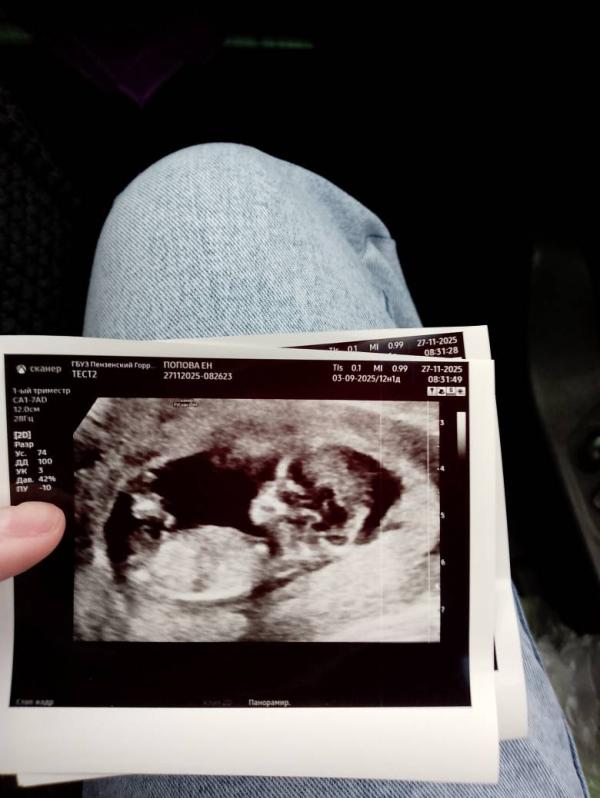

Дорогие мамы! Кто делал УЗИ у Сафронова Евгения Николаевича. У нас сегодня был первый скрининг и он предположил пол ребенка. Поделитесь вашим опытом, кому предполагал, у кого потом совпало, у кого нет? 🌞

Да. Передо мной пара вышла, я подслушала, что им мальчика предположил. Мне вот девочку😁 просто я вторым когда была беременна, в 16 недель платно на узи пола пошла к рандомному доктору, сказал, что девочка, а на втором скрининге другой врач увидел мальчика и не ошибся. Вот, боюсь сглазить😁

Да я и смотрю, вроде между ножек пирожок )

Нам тоже в 12 недель сказали девочка, но муж ещё надеется на второй скрининг и там вдруг мальчик окажется))